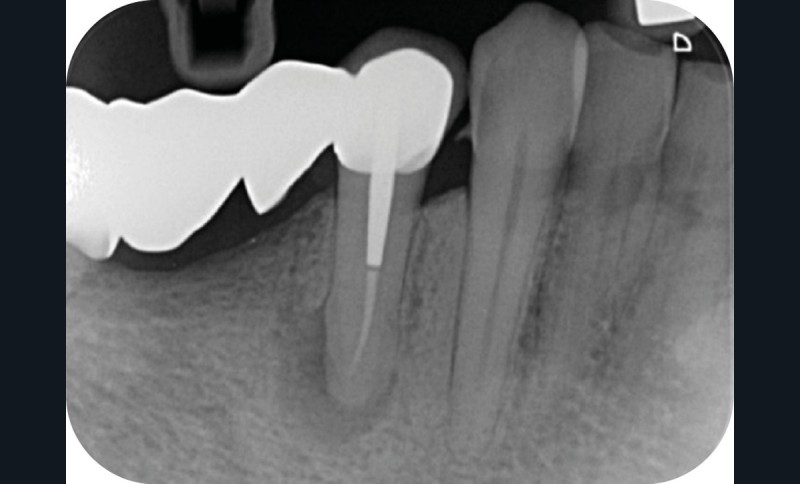

Une patiente de 56 ans, sans antécédents médico-chirurgicaux, se présente au Centre de soins dentaires pour cause de douleurs secteur 4. Les examens cliniques et radiographiques permettent d’orienter le diagnostic vers un abcès apical aigu sur la dent n°44 et de suspecter la présence d’un canal lingual non traité. Cette dent est support d’un bridge de grande étendue, de la dent n°44 à 47, étanche et apportant pleine satisfaction à la patiente (fig. 1).

La cavité d’accès endodontique était alors traditionnellement réalisée en se figurant les axes de la racine et du bridge (fig. 2). Cette aptitude à s’orienter dans l’espace n’est cependant pas aisée, et différents outils numériques offrent aujourd’hui la possibilité de dessiner la trajectoire suspectée du canal sur les coupes de l’examen Cone Beam et d’aider le praticien à planifier son futur geste thérapeutique (fig. 3, 4). Après pose du champ opératoire, une voie d’accès est ainsi réalisée à travers le bridge en reportant les mesures de la planification 3D (fig. 5). Le tenon est déposé par vibration avec un insert ultrasonore puis la lecture des teintes dentinaires sous microscope permet d’objectiver la présence d’un canal supplémentaire non traité (fig. 6). Les surplombs dentinaires sont supprimés avec un insert ET18D (Actéon) et les entrées canalaires relocalisées avec une lime rotative d’évasement coronaire.